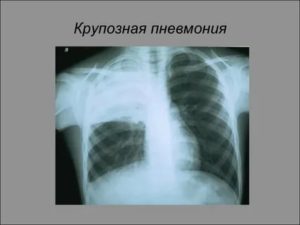

Плевропневмония симптомы и лечение

Существует пневмония – воспаление легких. Что такое плевропневмония? Это воспаление одного (и более) долей легких с вовлечением плевры (при котором развивается плеврит). Данное заболевание является тяжелой формой пневмонии, но протекает по воспалительному типу. Обладает вирусной (пневмококковой) природой. Имеет другие названия: крупозная, пневмококковая или частичная пневмония.